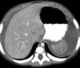

Peritoneal fluid

Peritoneal fluid is a serous fluid made by the peritoneum in the abdominal cavity which lubricates the surface of tissue that lines the abdominal wall and pelvic cavity. It covers most of the organs in the abdomen. [Source: Wikipedia ]